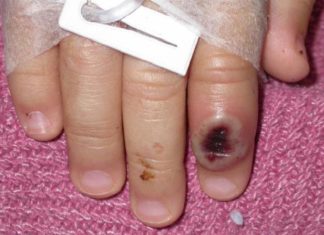

Detectado en Florida un posible caso de viruela del mono

Miami, EE.UU.- Las autoridades sanitarias de Florida detectaron un presunto caso de viruela del mono en el condado Broward, en el sur de este...

EEUU reporta primer caso de viruela símica en Massachusetts

Nueva York, EE.UU. — Massachusetts reportó el miércoles un raro caso de viruela símica en un hombre que viajó recientemente a Canadá, y los...